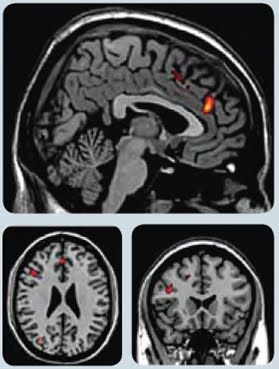

فى كلا الحالتين السابقتين تم التقاط صور لمخ الأشخاص تحت التجربة و لوحظ نشاط زائد في منطقة في المخ معروفة بإسم القشرة الحزامية الامامية في الأشخاص الذين شاهدو الخدعة السحرية عن الأشخاص الذين شاهدوا المشاهد العادية، لذا فيعتقد أن هذه المنطقة من المخ ذات دور هام في تحليل العلاقات المنطقية بين الأشياء و الأحداث لمختلفة في حياتنا.